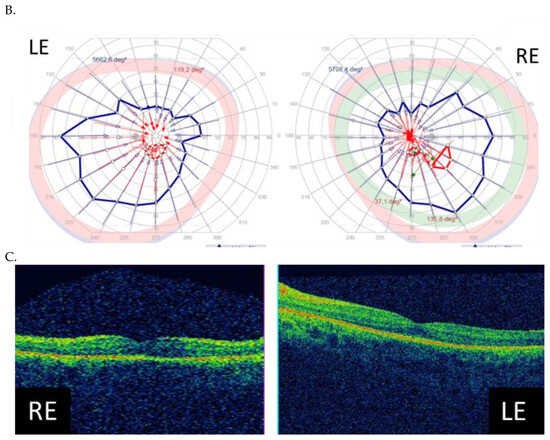

| I (family 1) | c.2442_2445del | 10 | 31 | 0.7 0.7 | Advanced constriction, only V4e remarkable | 277 264 |

| II (family 2) | c.2340_2341del | 12 | 42 | 0.01 0.01 | Advanced constriction, only V4e remarkable | 208 205 |

| III (family 3) | c.2587G>T | 8 | 36 | 0.5 0.6 | Middle constriction, V4e, III4e and I4e remarkable | 143 147 |

| IV (family 4) | c.2389dup | 10 | 22 | 0.7 0.7 | Middle constriction, V4e, III4e remarkable | 223 225 |

| V (family 4) | c.2389dup | 10 | 22 | 0.4 0.2 | Middle constriction, V4e, III4e and I4e remarkable | 260 240 |

| VI (family 5) | c.2455dup | 14 | 25 | 0.6 0.3 | Middle constriction, V4e, remarkable | 205 186 |

| VII (family 6) | c.593G>T | 12 | 20 | 0.5 0.5 | Middle con-striction, V4e, III4e and I4e remarkable | 250 245 |

| VIII (family 7) | c.799G>C | 6 | 47 | 0.2 0.3 | Middle con-striction, V4e, III4e and I4e remarkable | 240 230 |